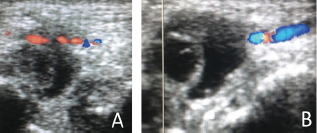

Figure 3: Ultrasonography with Doppler in A and B demonstrating pseudo aneurysm with thrombosis in the distal radial artery.

A 69 years old man with right wrist pain and functional limitations for 06 months. Finkelstein, Tineland Phalentests were negative. Important edema in the wrist and hand at physical examination (Figure 1). Ultrasonography demonstrated pseudo aneurysm with thrombosis in the distal radial artery (Figures 2 & 3).